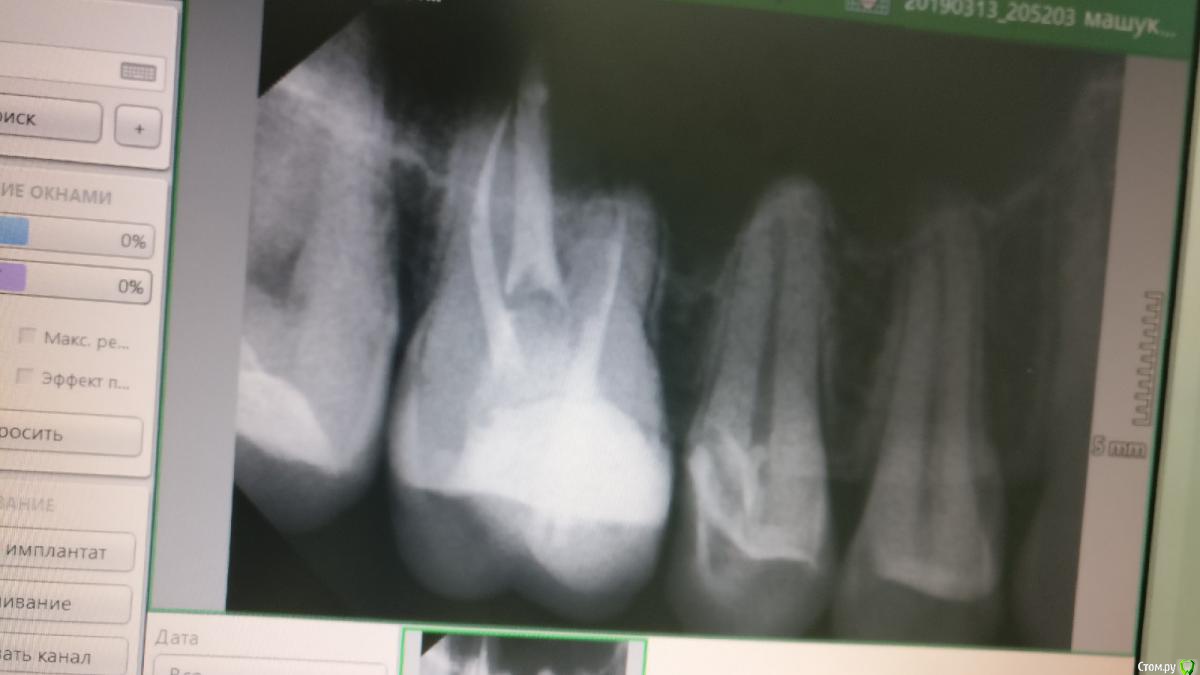

mgennady Опубликовано 14 марта, 2019 Поделиться Опубликовано 14 марта, 2019 13.03.19 Пришел в клинику (клиника профессорская, лечение проводят стажеры) с целью вылечить кариес, который был обнаружен двумя днями ранее. (Никаких жалоб с моей стороны не было, зубы не болели). Весь процесс лечения я наблюдал на телевизоре. Снимок мне не делали.Оказалось что в зубе (зуб 1-5) кариес дошел до дентина, обнажились две кровящиеся дырочки (кровь шла не долго, порядка 7 секунд). Стоматолог принял решение наложить на отверстия препарат РУДЕНТ и сверху наложить временную пломбу. В процессе я заметил, что с этими дырочками обращаются аккуратно, не трогают их зондом и другими инструментами, внутри не ковыряются. Однако в процессе накладывания препарата стоматолог с силой вдавливал препарат в эти отверстия, это меня напрягло, но боли в тот момент я, конечно, не чувствовал. По окончании приема стоматолог объяснил мне, что ему неизвестно проникла ли инфекция вглубь, поэтому он наложил препарат и записал меня на 15 число, объяснив, что если будут постоянные боли до 15 числа, то очистят канал, а если болей не будет, то поставят пломбу.После выхода из клиники сразу начались боли в ухе и виске. А через час, после того как отошла анестезия начался ад. Я был готов к боли, мне до этого делали операцию в ротовой полости и боль в послеоперационный период была терпимой, но эта боль была невыносимой, сильнее боли я в жизни не испытывал, я даже просто не мог сидеть или лежать, мог только ходить по комнате туда сюда. Болели обе челюсти (болел симметричный зуб на другой челюсти), часть языка, часть горла, висок и ухо. Начал пить Кеторолак, но он полностью не избавлял от боли, к тому же эффект 1 таблетки длился около 2 часов и дальше снова начинался ад. Я написал стоматологу, он ответил "это плохо" и перенес прием на 14 число на 2ую половину дня. Я продолжал мучиться. Когда наступил вечер я не выдержал и поехал в какую-то круглосуточную стоматологию где мне сделали снимок и поставили анестезию, чтобы я хоть сколько-нибудь поспал (удалось поспать 3 часа). На снимке мне показалось странным, что РУДЕНТ так глубоко запихан в зуб и возникло предположение, что, может быть у меня такие боли именно из-за того, что мне так старательно напихали этого препарата.Дождавшись 7 утра я записался в другой филиал этой клиники и сразу же поехал туда. Там посмотрели на снимок и сказали, что так и должно быть, что тот стоматолог все правильно сделал и что у меня просто инфекция так себя проявляет. Вычистили канал, поставили временную пломбу и отправили домой.Снимок прикреплен ниже (второй файл это тоже снимок, но с пририсованными мной пояснениями).Вопросы:1) Мог ли действительно не болящий и никак по другому не проявляющий себя зуб оказаться настолько глубоко испорченным?2) Действительно ли нормально проверять есть ли в канале инфекция путем наложения препарата, который возможно вызовет адские боли, и отпусканием пациента домой на 2 дня? Нет ли никаких других способов?3) Должен ли препарат РУДЕНТ настолько глубоко запихиваться в эти отверстия (кажется стоматологи называли их скрытыми точками)? Или же нужно было просто запечатать им отверстия? Могло ли это запихивание быть причиной болей?Извините, что получилось так длинно, я боялся пропустить что-нибудь важное.Заранее спасибо. Ссылка на комментарий